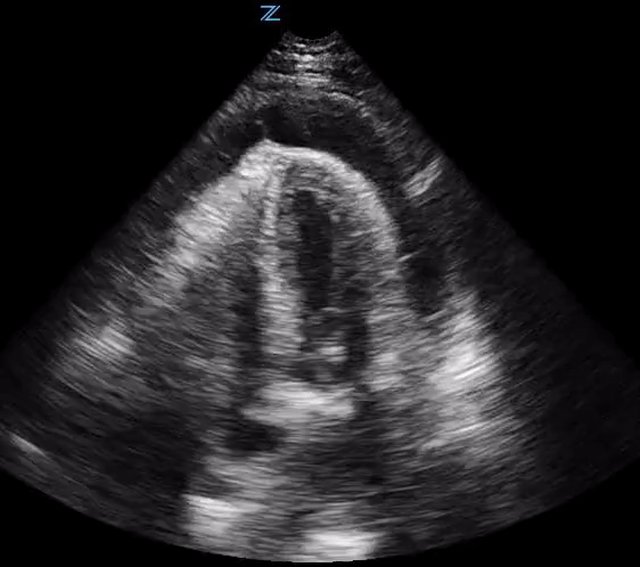

Pericardial effusion is seen anterior to the descending aorta as portrayed in image. Pleural effusion is posterior to the descending aorta.

• Size:

• Small < 1cm. Volume 50-100 ml

• Moderate 1-2 cm. Volume 100-500 ml

• Large >2cm. Volume > 500ml